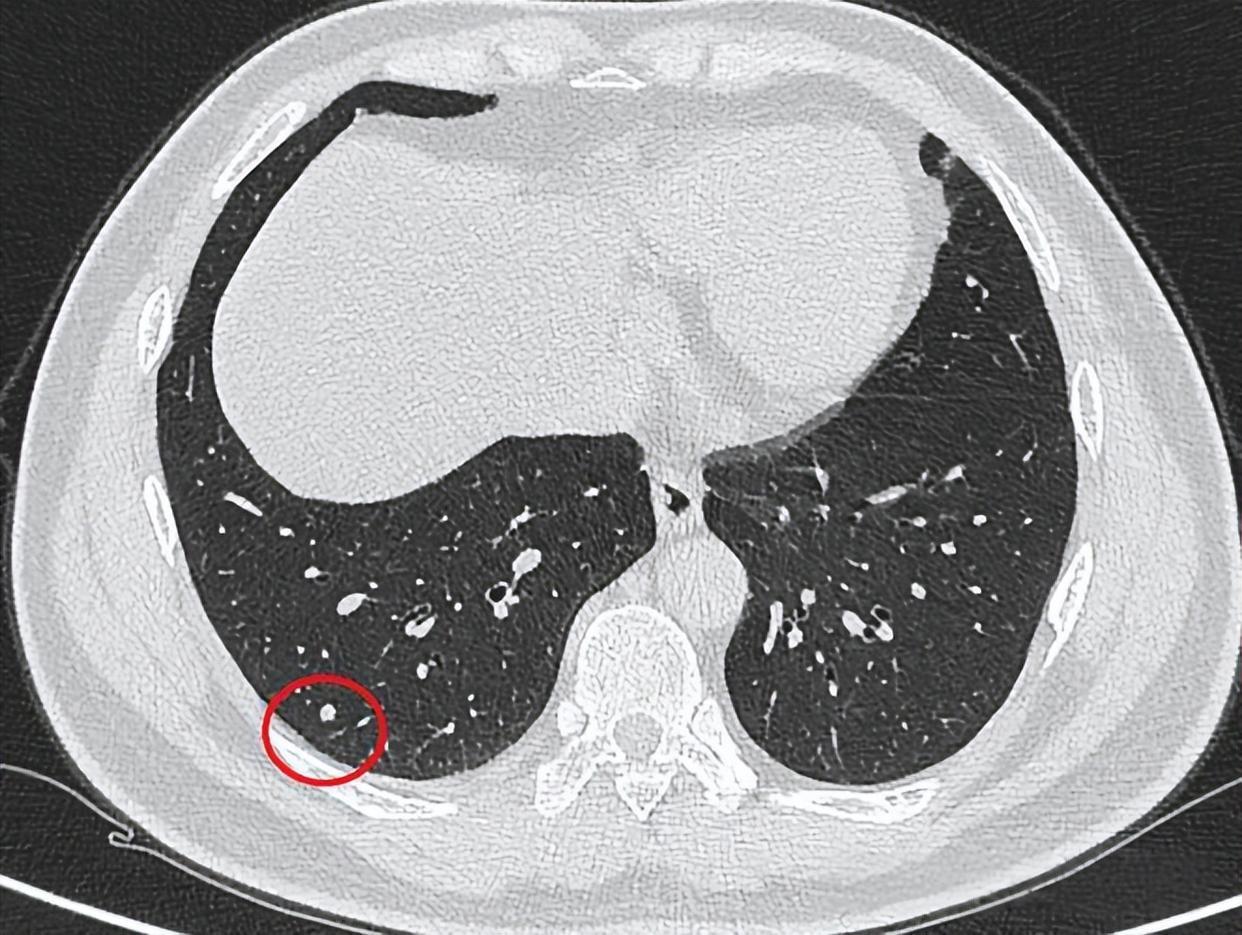

磨玻璃结节,是指在CT影像上看到的一派“隐约影”,像蒙了一层雾,透过这层雾还能看到后头的血管和支气管纹理。

磨玻璃结节的分型

根据身分不同,磨玻璃结节分为三类:

要点来了:纯磨玻璃结节,即即是恶性,也频繁属于“惰性癌”——助长极慢,多年不变化,对生命实在莫得恫吓。

中国《肺结节调理民众共鸣》明确指出:关于直径<8mm的纯磨玻璃结节,不提出立即手术,保举按时随访。

李姐的结节是6mm的纯磨玻璃结节,恰巧属于这一类型。是以大夫的判断是:随访不雅察,无须措置。